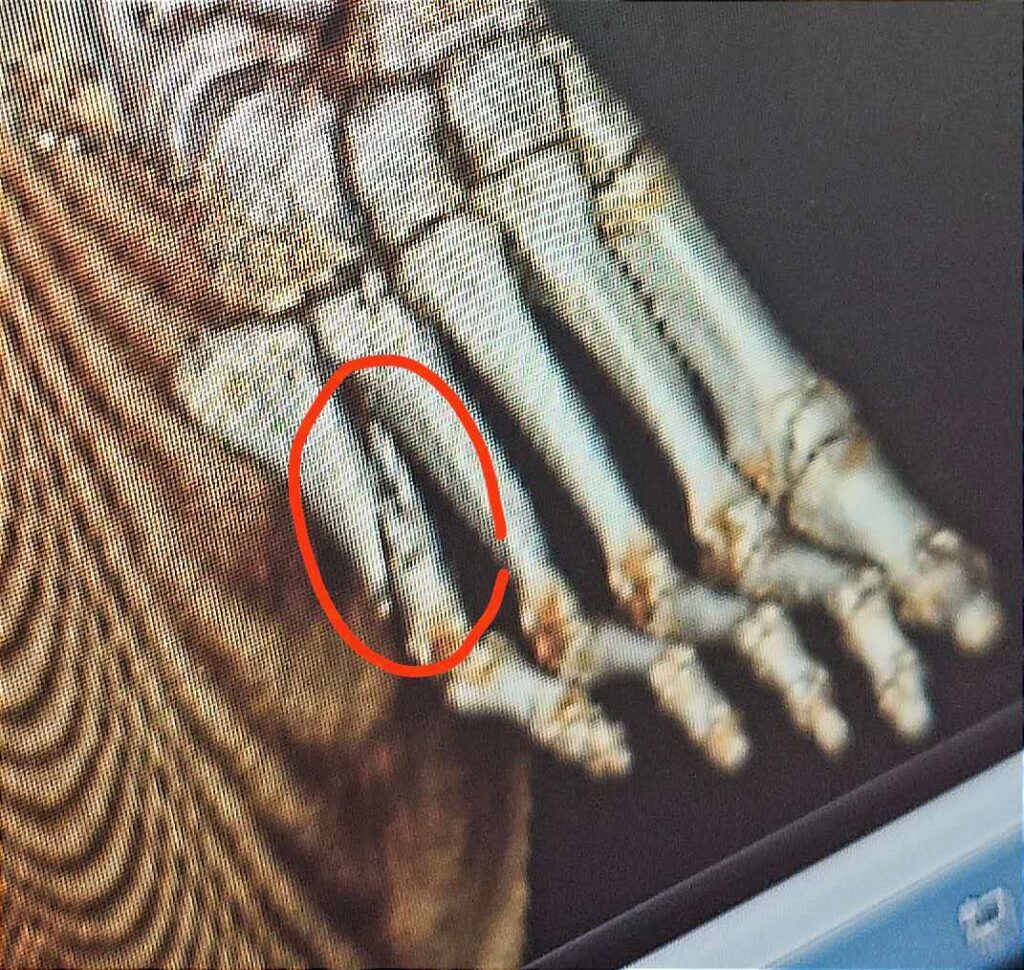

Four days after the injury, I finally went to the emergency room. An X-ray revealed a spiral fracture of the fifth metatarsal and the need for urgent surgery. I wasn’t allowed to go home; instead, I was admitted to a hospital room, where I waited for the operation two days later.

After the surgery, I was “richer” by a metal plate in my foot—this one made in China. Although a longer hospital stay was recommended, I asked for an early discharge. The doctor agreed, and I was able to leave the hospital just two days after the operation, with help from my friend Ken.

Such a small bone, yet such a long recovery. Today, I can do almost everything again, but I still haven’t dared to play basketball. After any surgery, the body functions—but never quite the same as before. Unfortunately, that’s just how it is.